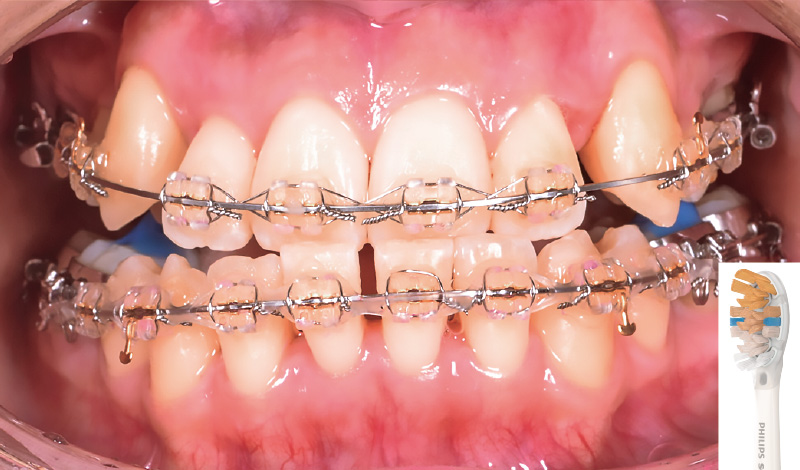

症例1-3 「ソニッケアー」によるブラッシング直後(替ブラシは「プレミアムオールインワンブラシ」を使用)。プラークの付着はほぼ見られない。 -

症例1-4 「プレミアムオールインワンブラシ」は隣接面にも当てやすく、「ソニッケアー」導入前と比べてプラークコントロールはかなり改善された。